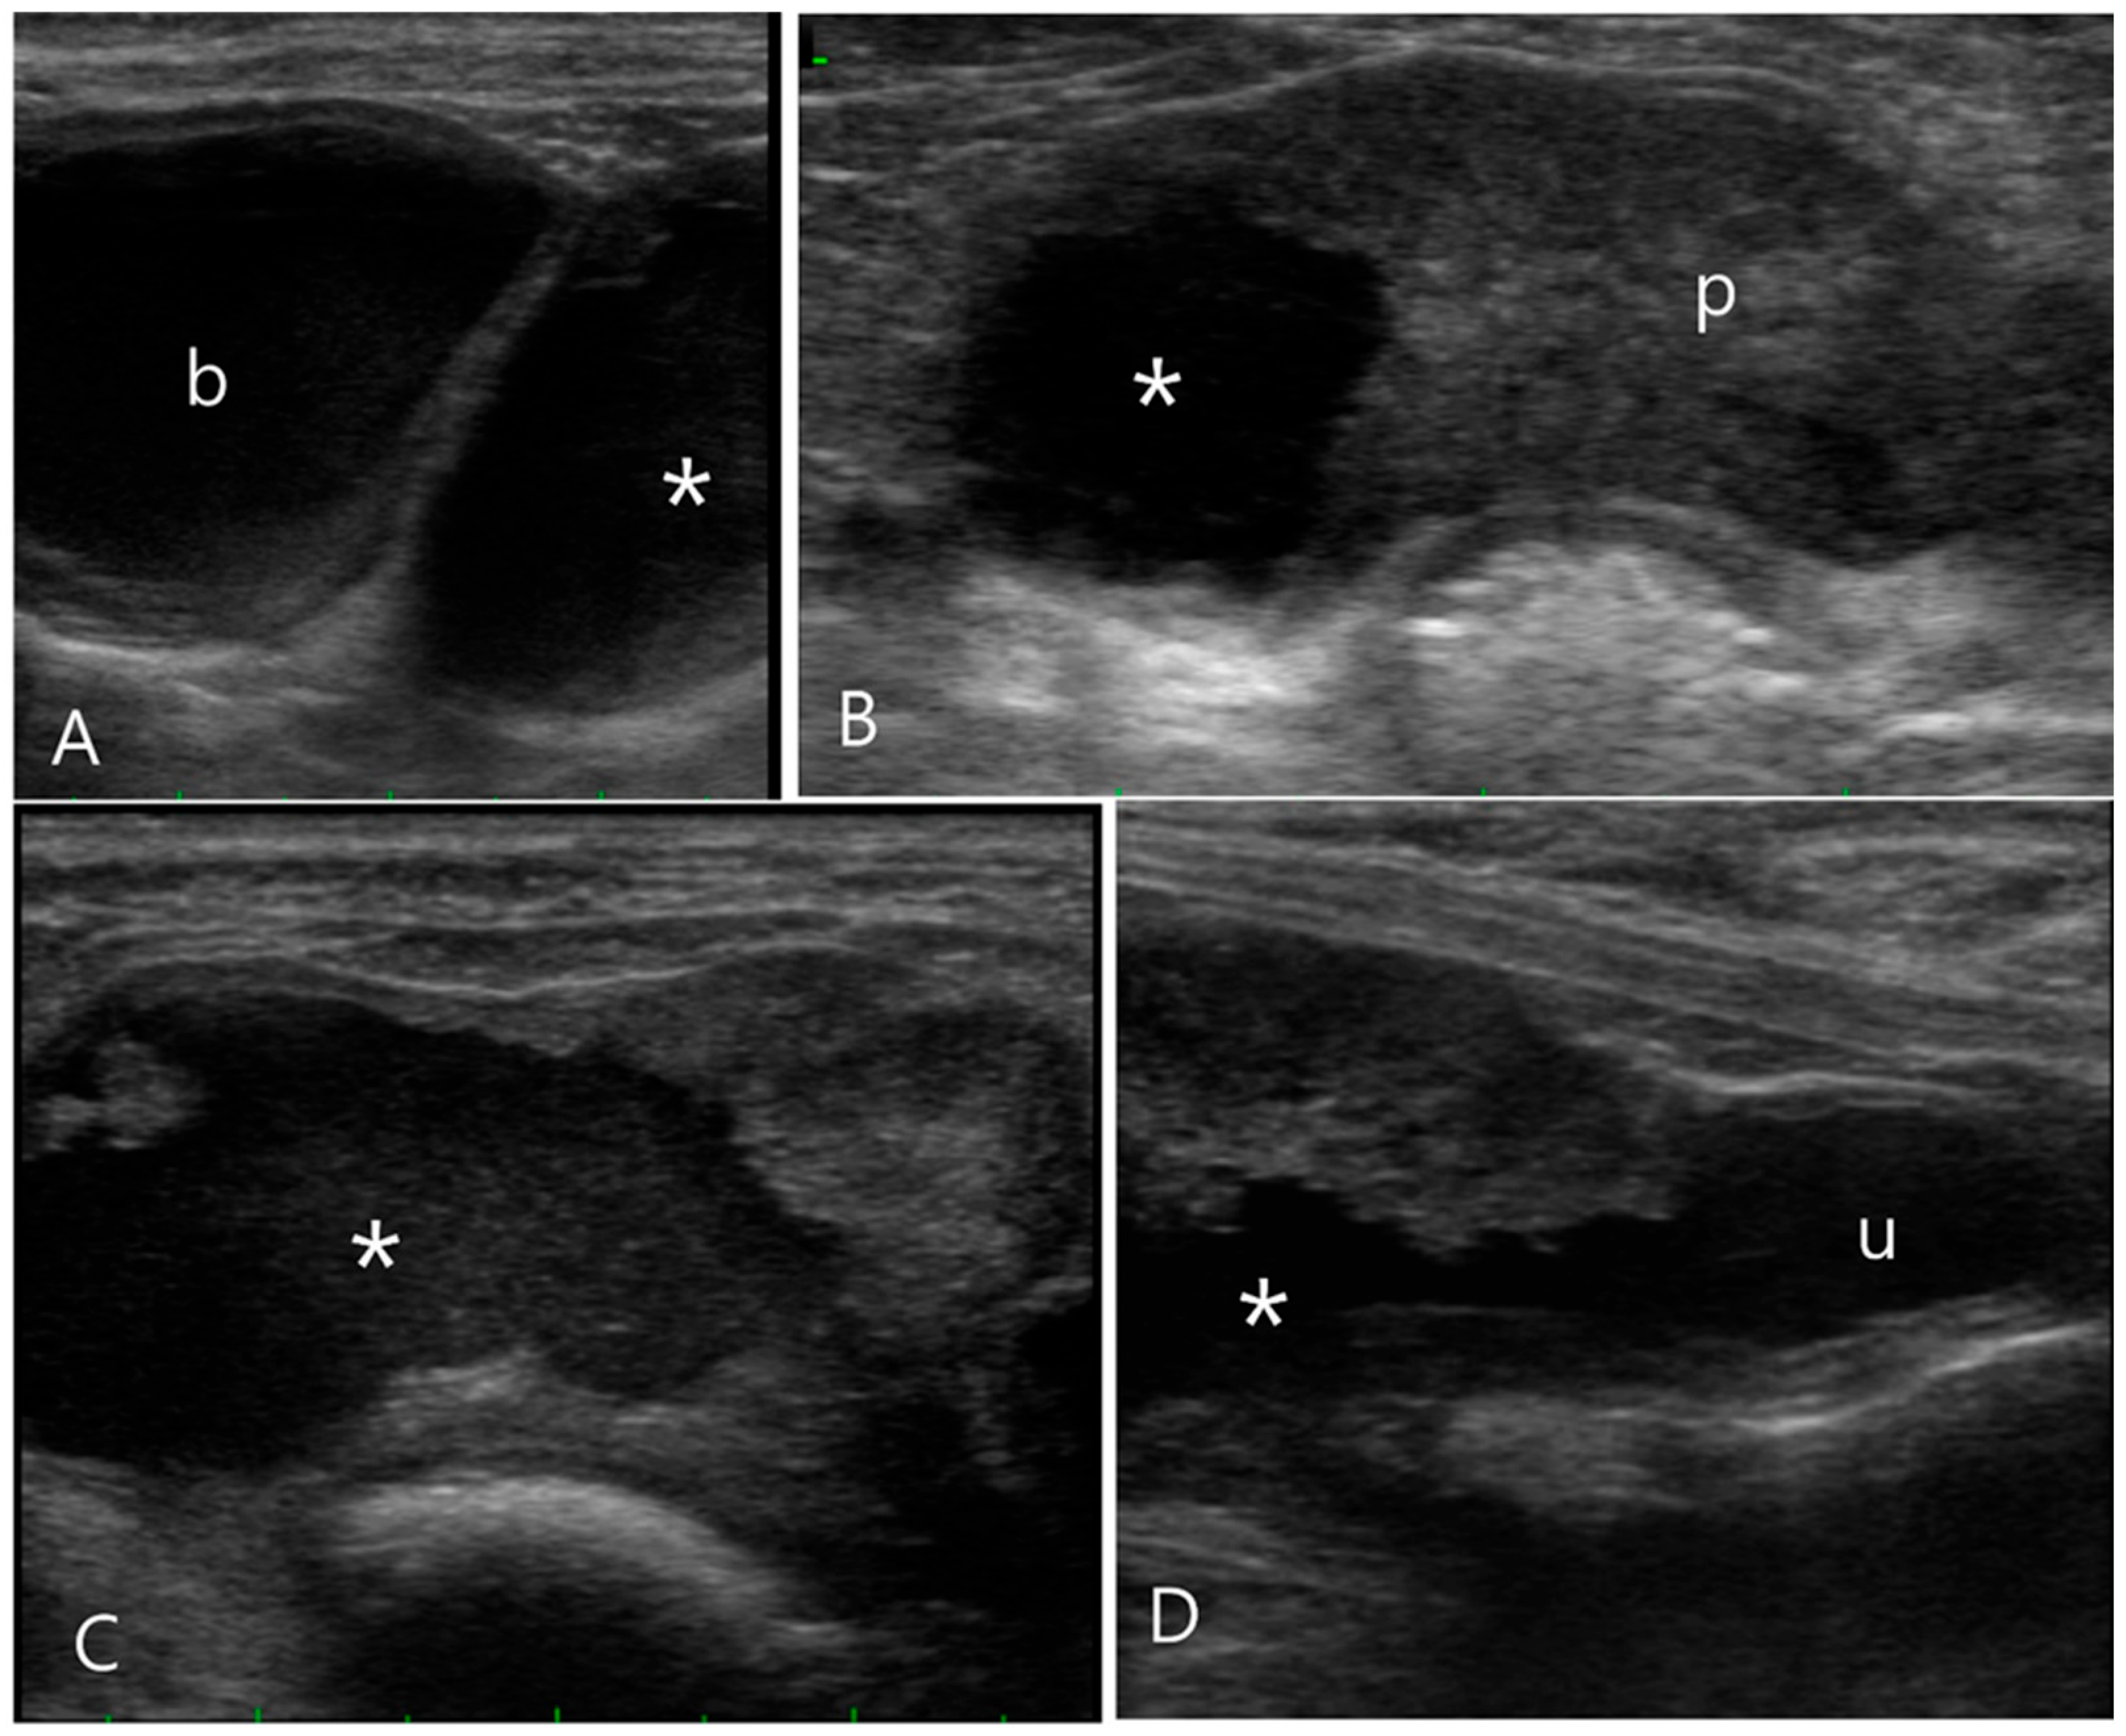

2.3. Case 3